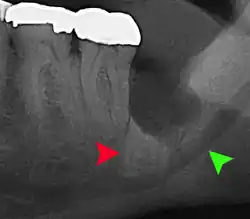

Panoramic radiograph of impacted lower wisdom teeth (green arrows) in a 26-year-old with dental caries (red arrows) on the adjacent teeth

The diagnosis of impaction can be made clinically if enough of the wisdom tooth is visible to determine its angulation, depth, and if the patient is old enough that further eruption or uprighting is unlikely. Wisdom teeth continue to move to the age of 25 years old due to eruption, and then continue some later movement owing to periodontal disease.[18]

If the tooth cannot be assessed with clinical exam alone, the diagnosis is made using either a panoramic radiograph or cone-beam CT. Where unerupted wisdom teeth still have eruption potential several predictors are used to determine the chance of the teeth becoming impacted. The ratio of space between the tooth crown length and the amount of space available, the angle of the teeth compared to the other teeth are the two most commonly used predictors, with the space ratio being the most accurate. Despite the capacity for movement into early adulthood, the likelihood that the tooth will become impacted can be predicted when the ratio of space available to the length of the crown of the tooth is under 1.[5]: 141

Impacted 2nd molar (red arrow) with developing wisdom tooth (green arrow)

There is no standard to screen for wisdom teeth. It has been suggested, absent evidence to support routinely retaining or removing wisdom teeth, that evaluation with panoramic radiograph, starting between the ages of 16 and 25 be completed every 3 years. Once there is the possibility of the teeth developing disease, then a discussion about the operative risks versus long-term risk of retention with an oral and maxillofacial surgeon or other clinician trained to evaluate wisdom teeth is recommended. These recommendations are based on expert opinion level evidence.[19] Screening at a younger age may be required if the second molars (the "12-year molars") fail to erupt as ectopic positioning of the wisdom teeth can prevent their eruption. Radiographs can be avoided if the majority of the tooth is visible in the mouth.